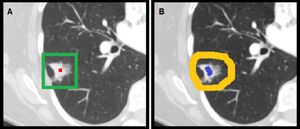

Lung Tumor Segmentation Methods: Impact on the Uncertainty of Radiomics Features for Non-small Cell Lung Cancer

Publication: PLoS One. 2018 Oct 4;13(10):e0205003. PMID: 30286184 | PDF Authors: Owens CA, Peterson CB, Tang C, Koay EJ, Yu W, Mackin DS, Li J, Salehpour MR, Fuentes DT, Court LE, Yang J. Institution: Department of Radiation Physics, The University of Texas MD Anderson Cancer Center, Houston, Texas, USA. Abstract: PURPOSE: To evaluate the uncertainty of radiomics features from contrast-enhanced breath-hold helical CT scans of non-small cell lung cancer for both manual and semi-automatic segmentation due to intra-observer, inter-observer, and inter-software reliability. METHODS: Three radiation oncologists manually delineated lung tumors twice from 10 CT scans using two software tools (3D-Slicer and MIM Maestro). Additionally, three observers without formal clinical training were instructed to use two semi-automatic segmentation tools, Lesion Sizing Toolkit (LSTK) and GrowCut, to delineate the same tumor volumes. The accuracy of the semi-automatic contours was assessed by comparison with physician manual contours using Dice similarity coefficients and Hausdorff distances. Eighty-three radiomics features were calculated for each delineated tumor contour. Informative features were identified based on their dynamic range and correlation to other features. Feature reliability was then evaluated using intra-class correlation coefficients (ICC). Feature range was used to evaluate the uncertainty of the segmentation methods. RESULTS: From the initial set of 83 features, 40 radiomics features were found to be informative, and these 40 features were used in the subsequent analyses. For both intra-observer and inter-observer reliability, LSTK had higher reliability than GrowCut and the two manual segmentation tools. All observers achieved consistently high ICC values when using LSTK, but the ICC value varied greatly for each observer when using GrowCut and the manual segmentation tools. For inter-software reliability, features were not reproducible across the software tools for either manual or semi-automatic segmentation methods. Additionally, no feature category was found to be more reproducible than another feature category. Feature ranges of LSTK contours were smaller than those of manual contours for all features. CONCLUSION: Radiomics features extracted from LSTK contours were highly reliable across and among observers. With semi-automatic segmentation tools, observers without formal clinical training were comparable to physicians in evaluating tumor segmentation. "Three radiation oncologists manually delineated lung tumors twice from 10 CT scans using two software tools, 3D Slicer and MIM Maestro." |

User inputs for initializing semi-automatic segmentation tools (A) LSTK requires the user to select a seed within the tumor (red) to initiate the segmentation algorithm. Defining the maximum tumor radius generates a 3D bounding box (green) centered about the seed, within which the segmentation result will be confined. (B) GrowCut requires the user to label foreground (blue) and background (yellow) pixels to initiate the segmentation algorithm. Once labels were established, the GrowCut algorithm was followed by manual editing of the GrowCut-generated contours. Note that only the transverse view is shown here. Observers also labeled foreground and background pixels in the coronal and sagittal planes for each tumor case. |